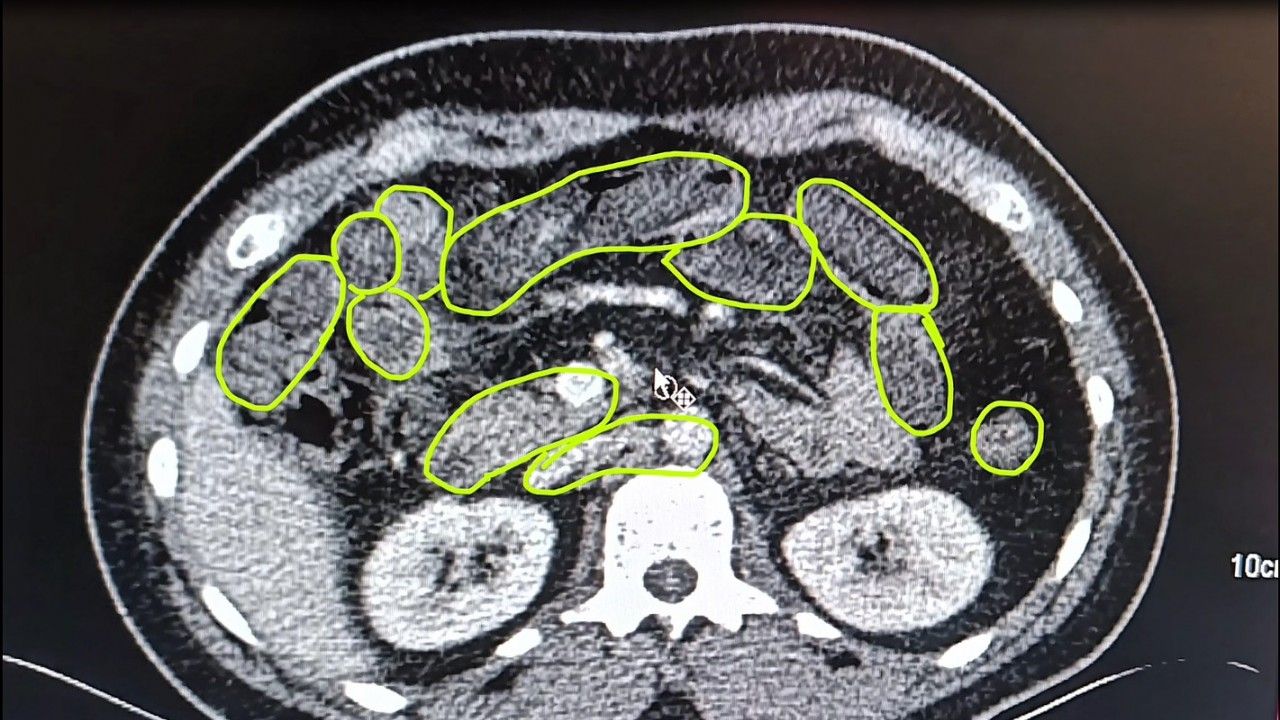

İl Jandarma Komutanlığı ekipleri, İran uyruklu A.O. (51), M.S. (37) ve P.S..'nin (28) ülkelerinden kente uyuşturucu getireceği bilgisine ulaştı. Şüpheliler Kocasinan ilçesi Himmetdede Mahallesi'nde taksi ile kente girmek istediği sırada durduruldu. Araçta yapılan aramada 15 gram esrar, 5 gram bonzai ve 117 adet uyuşturucu hap ele geçirildi. Gözaltına alınan 3 şüpheli muayene olmak üzere Kayseri Şehir Hastanesi'ne getirildi. Röntgen ve ultrason sonrası kontrollerde 3 şüphelinin midesinde uyuşturucu madde olduğu belirlendi. Şüphelilerin yuttukları uyuşturucuları kente sokmaya çalıştıkları tespit edildi. Kapsüller, sağlık ekibinin müdahalesiyle çıkarıldı. Taburcu edilen şüpheliler, İlçe Jandarma Komutanlığı'na götürüldü. (DHA)